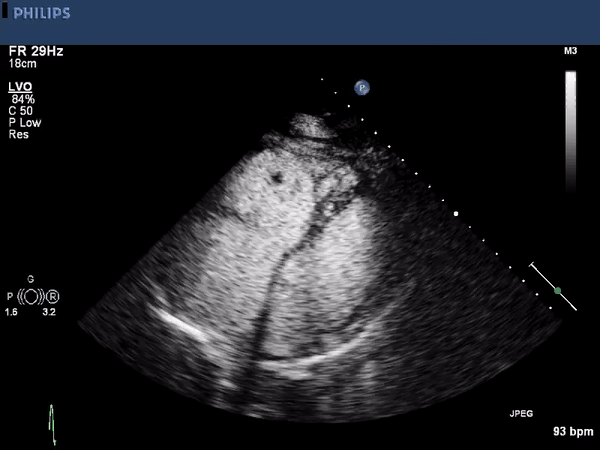

The echocardiographic images above show a large right ventricular

thrombus. The first image is a parasternal long axis view highlighting

the right ventricular inflow tract. A mobile thrombus is seen near the

anterior border. The other two images are using an apical approach

showing the right and left ventricle. Again a mobile the thrombus is

seen within the right ventricle. Contrast is used to enhance the

thrombus borders.